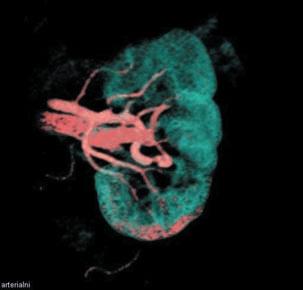

Aortální CT-angiografie je metodou volby (spolu s MR v některých indikacích). Je přesná s velkým rozsahem (od aortálního oblouku po femorální tepny). Vyšetření je možné doplnit kalibrací cév při plánování další intervenční léčby (například implantace stentgraftů do aneuryzmatu). Při požadavku na zobrazení pouze ascendentní aorty se s výhodou používá EKG triggering, který odstraňuje pohybové artefakty pulzující aorty. Mnohem lepší informace než při DSA jsou získány u disekce – průkaz entry a reentry, trombóza falešného lumina, zasahování do aortálních větví, ischemie orgánů. U aneuryzmat je možné přesně stanovit trombózu vaku a změřit jeho velikost. U typických případů se lze vyjádřit i k etiologii (ateromatóza, zánět, trauma). Sledujeme rovněž eventuální krvácení z vaku. Mezi další patologie indikované k zobrazení patří koarktace, posuzuje se její významnost, lokalizace, kolaterální oběh a další anomálie (perzistence d. Botalli). Častým nálezem jsou variace tepen odstupující z aortálního oblouku nebo variace aorty samotné. Při pooperačních vyšetřeních se sledují anastomózy aortálních náhrad, disekce, pseudoaneuryzmata, okolí aorty (obr. 1.7).